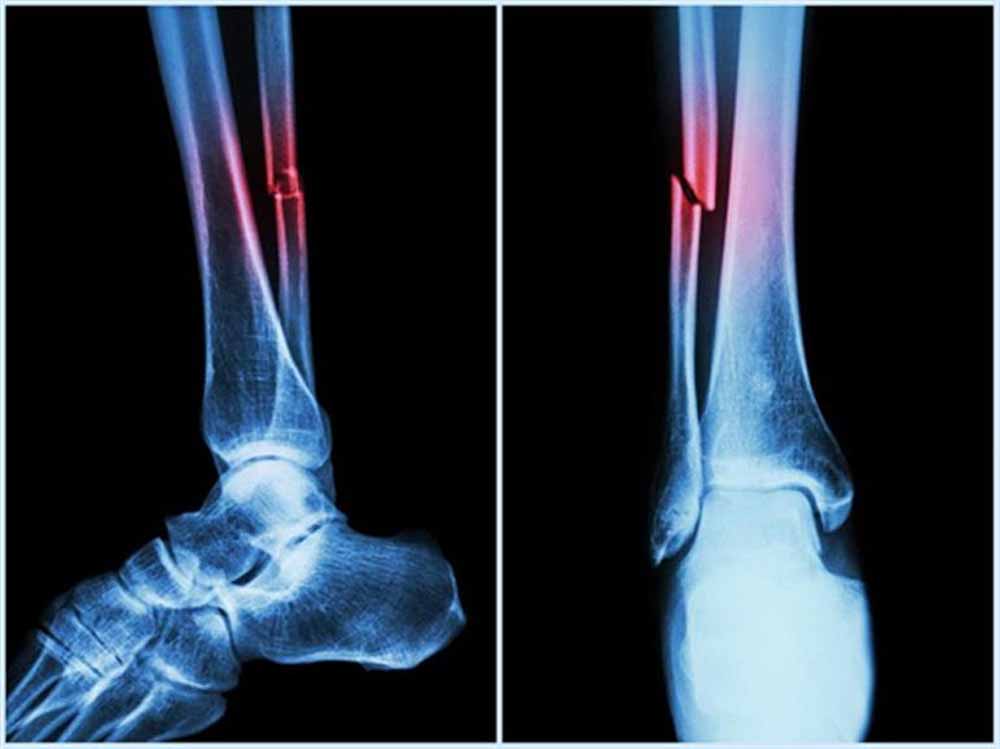

हालांकि सर्वोत्तम उत्पादकता के लिए इनका त्रि-आयामी आकृतियों में सटीक मुड़ना या खुलना आवश्यक है। प्रोटीन क्यों और कैसे खुलते हैं? यह समझना जीव विज्ञान का एक प्रमुख लक्ष्य है। इसका प्रभाव चिकित्सा, जैव प्रौद्योगिकी और ड्रग डिलिवरी पर पड़ता है। इस संदर्भ में हड्डी और उपास्थि के निर्माण, चोटों को ठीक करने और स्टेम कोशिकाओं को अस्थि-निर्माण कोशिकाओं में परिणत करने में बीएमपी-2 महत्वपूर्ण भूमिका निभाता है।

प्रो. हरेकृष्ण साहू ने इस शोध के निष्कर्षों और इससे संभावित वास्तविक लाभों के बारे में बताया कि बीएमपी-2 मनुष्यों में पाया जाने वाला एक महत्वपूर्ण प्रोटीन है। यह बोन टिश्यू के ग्लाइकोसामिनोग्लाइकन से सम्पन्न बाह्यकोशिकीय मैट्रिक्स में मौजूद रह कर हड्डियों के निर्माण और पुनर्निर्माण में बुनियादी भूमिका निभाता है।

बीएमपी-2 प्राकृतिक रूप से जीवों में और मुख्य रूप से एक प्रोटियोग्लाइकन कॉम्प्लेक्स का हिस्सा बन कर मौजूद रहता है। इसके परिणामस्वरूप जीएजी चेन्स के साथ इसकी परस्पर प्रक्रियाएं इसकी अनुकूलता की गतिविधि का अभिन्न हिस्सा हैं।

ये परस्पर प्रक्रियाएं प्रोटीन ऑस्टियोइंडक्टिव क्षमता को गंभीर रूप से प्रभावित करती हैं। जीएजी के कार्यात्मक समूह में संशोधन जैसे कि टार्गेटेड सल्फेशन ऐसी परस्पर प्रक्रियाओं को गहराई से नियंत्रित कर सकता है, जिसके परिणामस्वरूप भौतिक-रासायनिक तनाव में भी बेहतर संरचनात्मक स्थिरता मिलने के साथ-साथ जैव सक्रियता बनी रहती है।